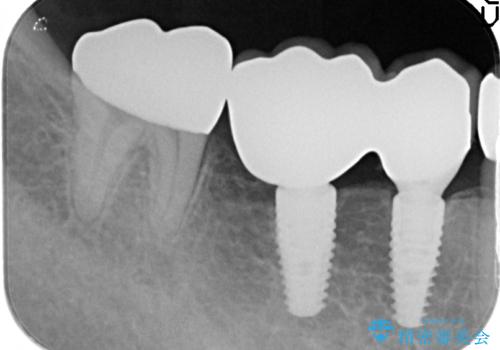

支台を増やし、残った歯の負担を減らし守るために欠損部位にインプラントを埋入し咬合力の負担に対応できる環境を整えます。

- 105.4万円(仮歯×4・ストローマンインプラント×2・チタンカスタムアバットメント×2・ジルコニアクラウン×4)費用は治療当時の料金となります

インプラント治療は、ブリッジや入れ歯と異なり人口の歯根となるインプラントを顎骨内に埋入することで咬合力に耐える支台を増やせるというメリットがあります。

残った歯の負担を減らすことでより長期的な予後を期待することができます。